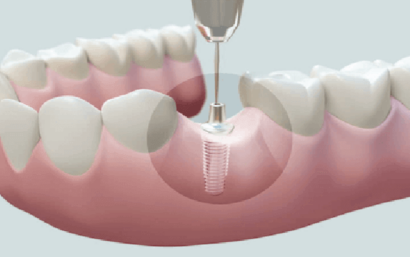

Mediante una restauración dental con un tratamiento de endodoncia podemos conservar el diente natural del paciente, evitando que tenga que ser sustituido por un implante dental.

Si la estructura del diente puede conservarse, la endodoncia permite eliminar la infección y mantener la pieza natural, evitando la extracción dental y la colocación posterior de un implante.